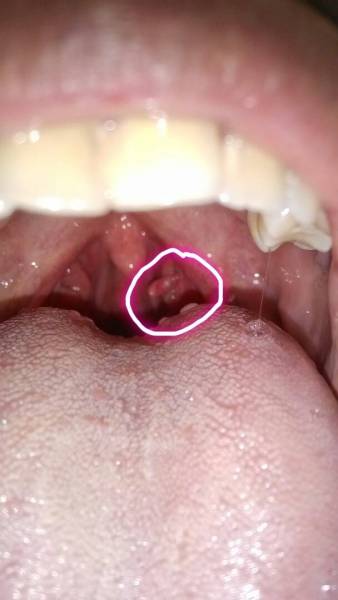

问:我嗓子里面长了个跟小舌头大小的东西,在左侧.是什么啊?怎么办?

喉咙左边的坨比右边的多大好多,后面还有一坨小肉和喉咙连在一起,有点

先天性双悬雍垂